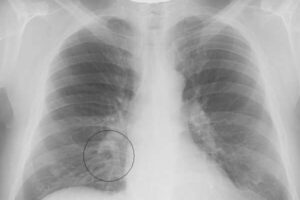

Лечение прикорневой пневмонии у детей

Высокая восприимчивость детей к различным инфекционно-воспалительным процессам является следствием их слабого и неразвитого иммунитета. Одна из самых опасных патологий — бронхопневмония. Заболевание коварное, ведь вовремя поставить диагноз сложно, так как воспаление находится в необычном месте — в корне легкого. Как протекает патология, как распознать первые симптомы? Узнайте об этих и других функциях в этой статье. …